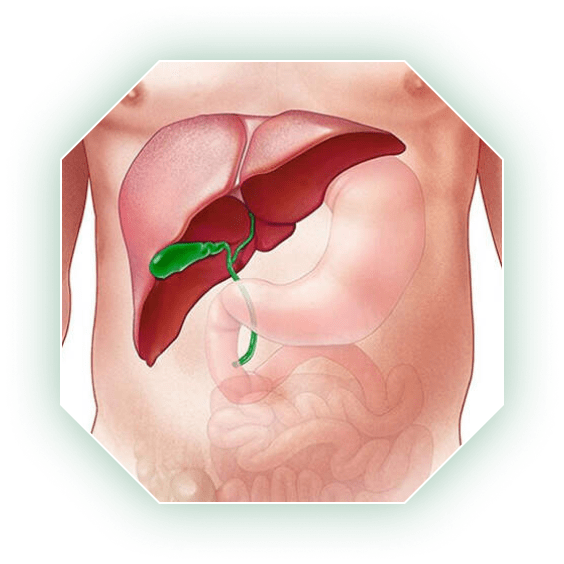

Анатомия и особенности Гартманова кармана желчного пузыря